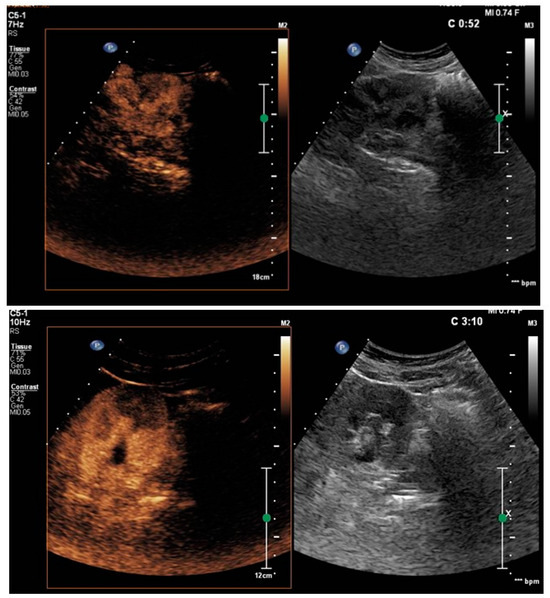

3. Results